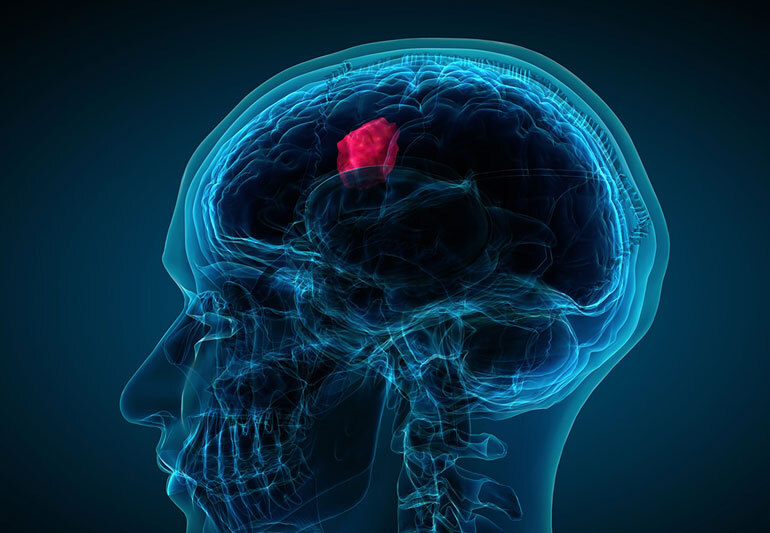

Как показало исследование, проведённое доктором Полом Бреннаном из Эдинбургского университета, тест под названием “Ноев ковчег» поможет понять, есть ли у человека опухоль мозга. Вовремя заметить это состояние важно, поскольку оно со временем может стать смертельно опасным.

Команда учёных под руководством доктора Пола Бреннана из Эдинбургского университета выяснила, что существует довольно простой способ узнать, развивается ли в мозге человека опухоль. Для этого проводится тест “Ноев ковчег».

У 87,5 % людей, которые показали плохие результаты в тесте (назвали менее 14 животных), обнаружилась опухоль мозга. При этом 48,1 % из тех, кто набрал высокий балл по итогам теста, этой опухоли не было. Всего в исследовании приняли участие 207 человек.